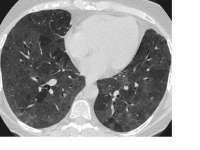

15802653050231.mp4 2159Кб, 384x848, 00:00:15

Окей, аноны: вот интересная статья, описывающая клиническую картину заболевших короной китайцев из Ухани:

https://marlin-prod.literatumonline.com/pb-assets/Lancet/pdfs/S0140673620302117.pdf

Исследовались 99 пациентов, все в одной клинике:

>Most patients were men, with a mean age of 55·5 years (SD 13·1; table 1). 50 (51%) patients had chronic diseases, including cardiovascular and cerebro vascular diseases, endocrine system disease, digestive system disease, respiratory system disease, malignant tumour, and nervous system disease

Перевожу: инфа о том, что вирус в первую очередь бьёт по мужчинам, — подтверждается;

что в первую очередь бьёт по старикам — подтверждается;

что в первую очередь бьёт по больным — не подтверждается (половина заболевших не имела никаких хронических болезней).

Использовалось следующее лечение:

76 % пациентов — антивирусные препараты (oseltamivir (75 mg every 12 h, orally), ganciclovir (0·25 g every 12 h, intra venously), and lopinavir and ritonavir tablets (500 mg twice daily, orally)в течение 3—14 дн.;

почти все пациенты — антибиотики (один вид или несколько разных);

13 пациентов — неинвазивная вентиляция лёгких;

4 пациента — инвазивная вентиляция лёгких;

Это означает, что большинству пациентов ИВЛ не потребовалась!

Наконец, вопрос, который всех интересует более всего: ЛЕТАЛЬНОСТЬ:

к 25.01 был выписан 31 % пациентов; 11 % ушли на поклон к Будде Пресветлому. Остальные пока остаются в больнице. Сведения обо всех них — на пикрелейтеде.

Кто умирает:

>The first two deaths were a 61­ year­ old man (patient 1) and a 69­ year­ old man (patient 2). They had no previous chronic underlying disease but had a long history of smoking. […] Of the remaining nine patients who died, eight patients had lymphopenia, seven had bilateral pneumonia, five were older than 60 years, three had hypertension, and one was a heavy smoker

Аноним 30/01/20 Чтв 12:50:09 170113 250